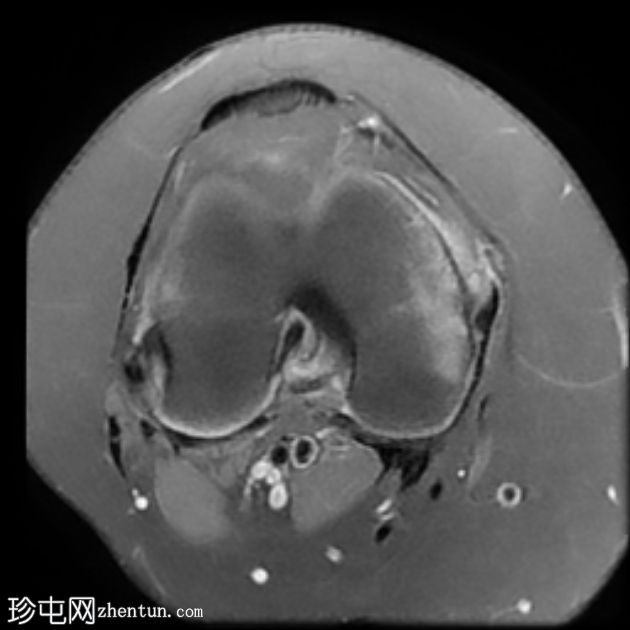

4.jpeg

矢状位

T1

股骨远端干骺端横向应力骨折线,在所有脉冲序列(T1、T2和STIR)上均呈低信号。其周围有骨髓水肿样信号。邻近骨膜软组织呈水肿样信号。